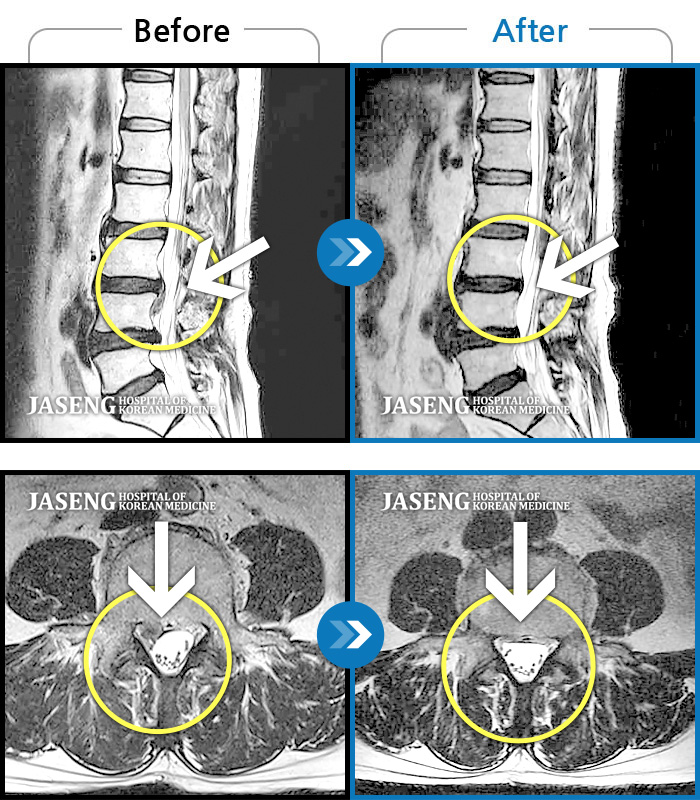

허리디스크

안산 · 김민수 원장

어떤 자세에도 통증이 지속되었다.

촬영시기

2018.10.25 ~ 2024.06.19

2024.07.31

조회수 509